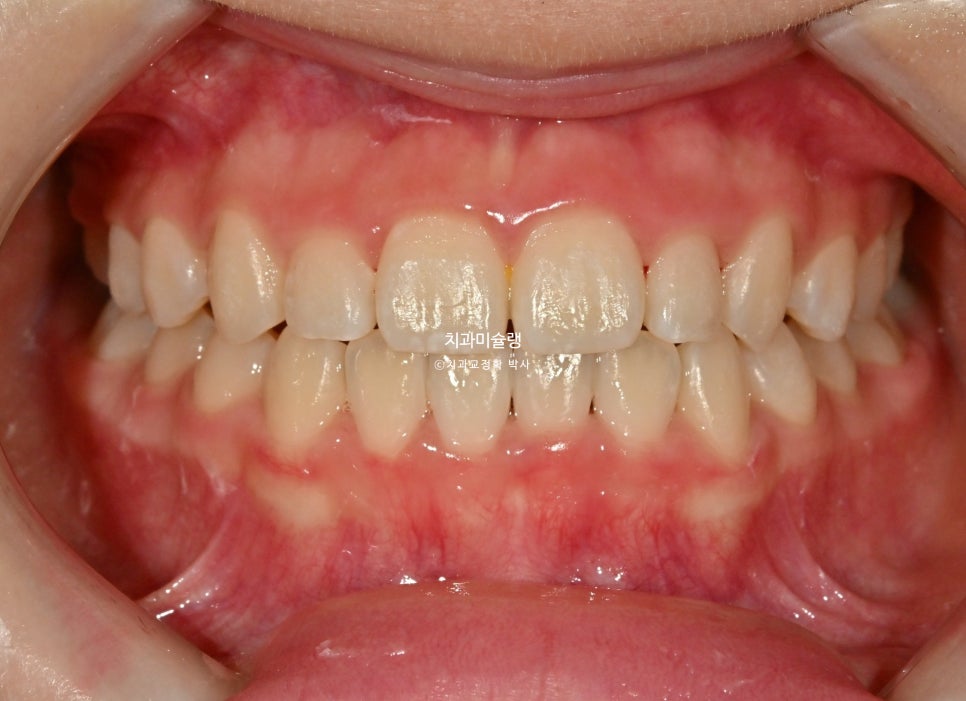

치료 완료 시 결과

중심선은 잘 맞으며 절단교합으로 인항 개방교합은 해소되었습니다.

어금니 교합관계는 1급을 달성.

3급 교합관계를 1급으로 만들기 위해 치료기간 내내 3급 고무줄을 사용했습니다.

결과가 성인교정치료 결과에 준한만큼 유지장치도 성인과 동일하게 들어갑니다.